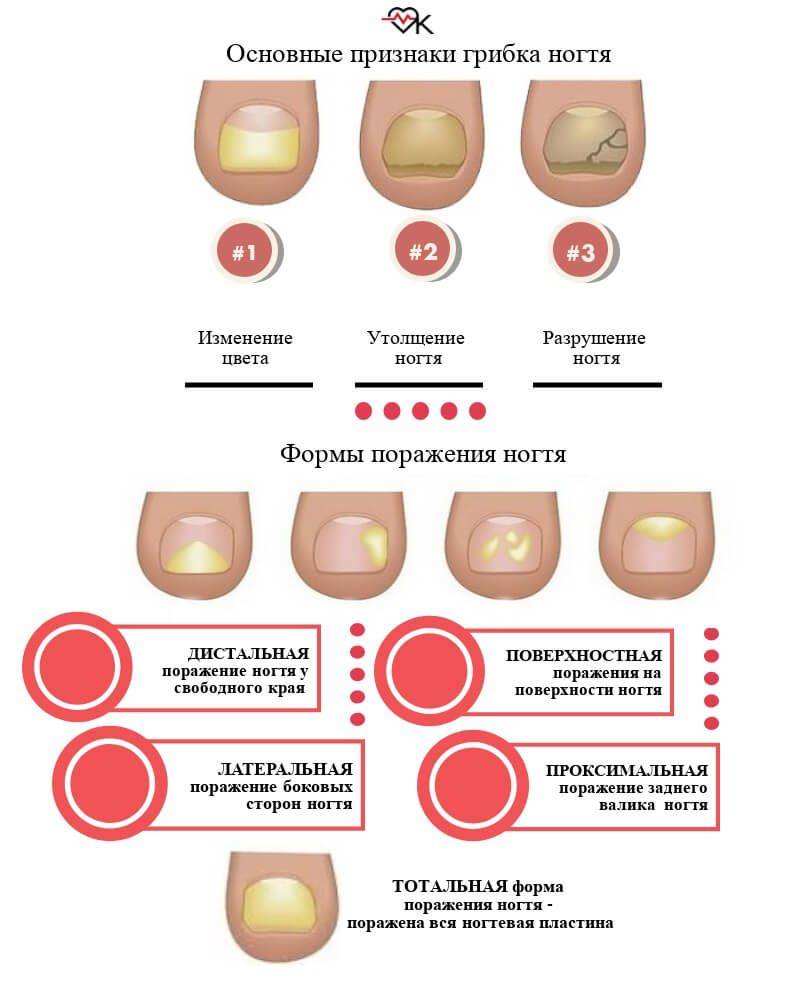

Грибковые заболевания ногтей: буклет с информацией